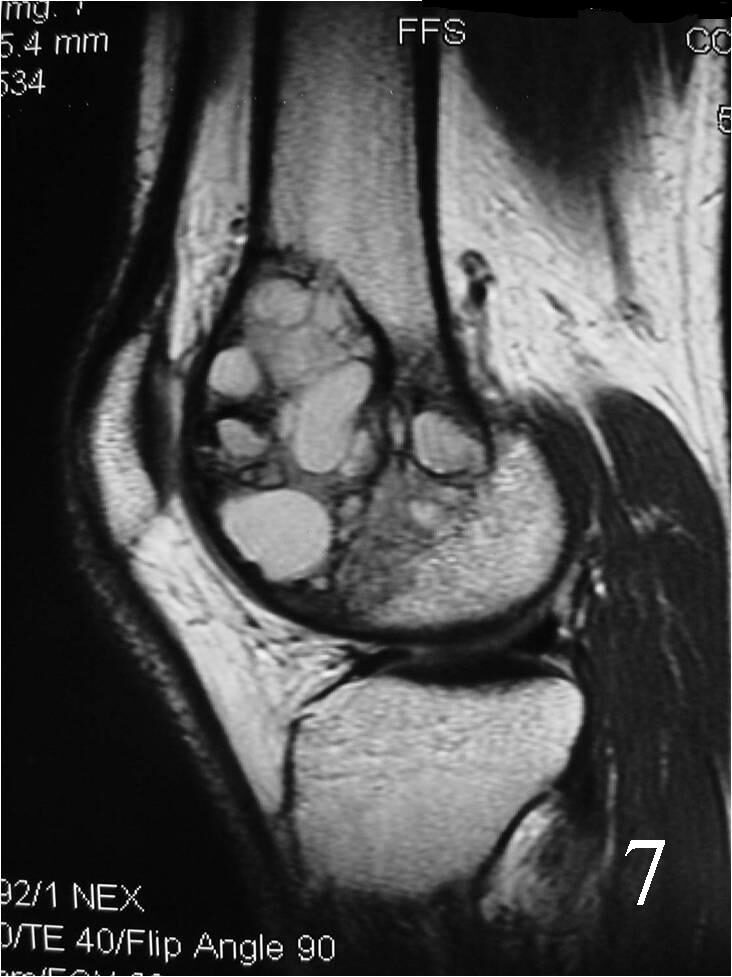

- Possible fluid-fluid level ( associated with secondary ABC) (Fig. 7, 8)

Fig. 7 Sagittal proton density MRI demonstrates cystic degeneration typical of a GCT

Fig. 8 Sagittal T2 MRI with fluid – fluid levels detected, indicative of ABC changes or secondary ABC component. There is posterior soft tissue extension. The soft tissue component is surrounded by periosteum.